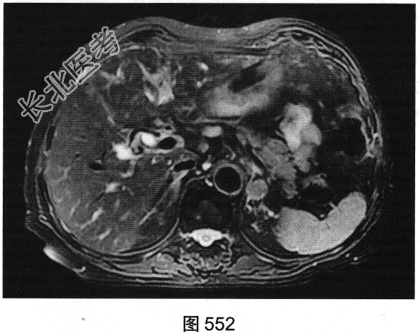

- 多项选择题3.[提示]MRI平扫+增强(图550~图555):T1WI正相位, 左侧肾上腺外侧肢可见类圆形T1WI稍高信号结节。T1WI反相位,结节信号明显减低。T2WI脂肪抑制, 结节呈均匀低信号。动态增强,动脉期结节轻度均匀强化, 静脉期结节呈相对低信号,延迟期结节呈相对低信号。可考虑的鉴别诊断为( )